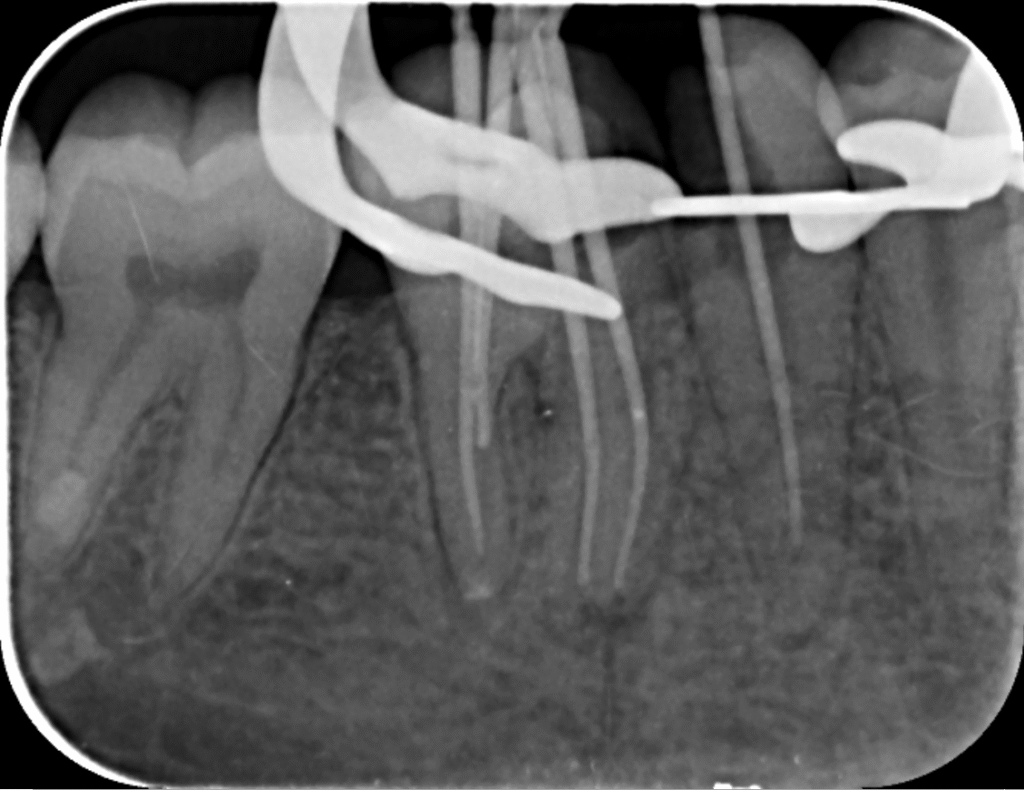

حذف مواد پرکننده قبلی

در این مرحله، دندانپزشک مواد پرکننده قبلی را از کانال‌های ریشه خارج می‌کند. این فرآیند ممکن است نیاز به ابزارهای خاصی داشته باشد تا کانال‌ها به طور کامل تمیز شوند. حذف مواد پرکننده قبلی مرحله‌ای حساس است که باید با احتیاط انجام شود تا آسیب به بافت‌های اطراف کاهش یابد.

پاکسازی و شکل‌دهی کانال‌ها

پس از حذف مواد پرکننده، کانال‌ها باید به طور کامل پاکسازی و شکل‌دهی شوند. این مرحله شامل استفاده از محلول‌های ضدعفونی‌کننده و ابزارهای خاص است. هدف از این مرحله حذف هر گونه باکتری و بافت مرده از کانال‌هاست.

بررسی مجدد وضعیت دندان

پس از پاکسازی، دندانپزشک دوباره وضعیت دندان را بررسی می‌کند تا اطمینان حاصل کند که تمام عفونت‌ها و باکتری‌ها از بین رفته‌اند. در این مرحله ممکن است دوباره تصاویر اشعه ایکس گرفته شود.